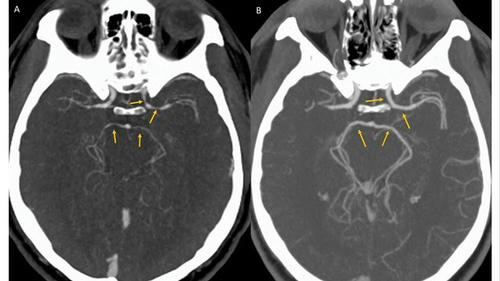

「世界一辛い」トウガラシを食べた男性の脳血管に狭窄が見つかった

(CNN)米ニューヨークで開かれたトウガラシの大食い大会で、世界一辛いといわれる「キャロライナ・リーパー」というトウガラシを食べた挑戦者の男性が、直後に激しい頭痛を訴えて病院に運ばれた。神経科の専門医が9日の医学誌BMJに発表した症例報告で明らかにした。

患者は34歳の男性で、頭と首の激しい痛みを訴えて病院の集中治療室に運ばれた。大会でキャロライナ・リーパーを食べた直後に後頭部に激痛が走り、頸部から頭部にかけてたちまち痛みが広がったという。

病院で検査した結果、脳出血や脳梗塞は起きていないことが判明。しかしCT血管造影を使って脳内の血管を調べたところ、左側の内頸(ないけい)動脈など脳につながる4本の血管に大きな狭窄(きょうさく)が見つかり、トウガラシが原因と思われる可逆性脳血管攣縮(れんしゅく)症候群(RCVS)と診断された。

専門家によると、RCVSは雷に打たれたような激しい頭痛を伴う疾患で、大抵は数日から数週間で回復するが、重症化すると命にかかわることもある。通常はトウガラシではなく、頭痛薬などの医薬品やコカインなどの違法薬物が関係する。

トウガラシに多く含まれるカプサイシンという化学物質は、身体の特定部位の血管を狭窄させる作用があることが分かっており、局所医薬品にも少量が使われる。

しかしトウガラシがRCVSを引き起こした症例の報告は今回が初めてだという。キャロライナ・リーパーの辛さはハラペーニョの400倍以上といわれている。

男性は治療を受けて快方へ向かい、数日後に退院した。5週間後の検査では、血管狭窄の症状は解消されていたという。